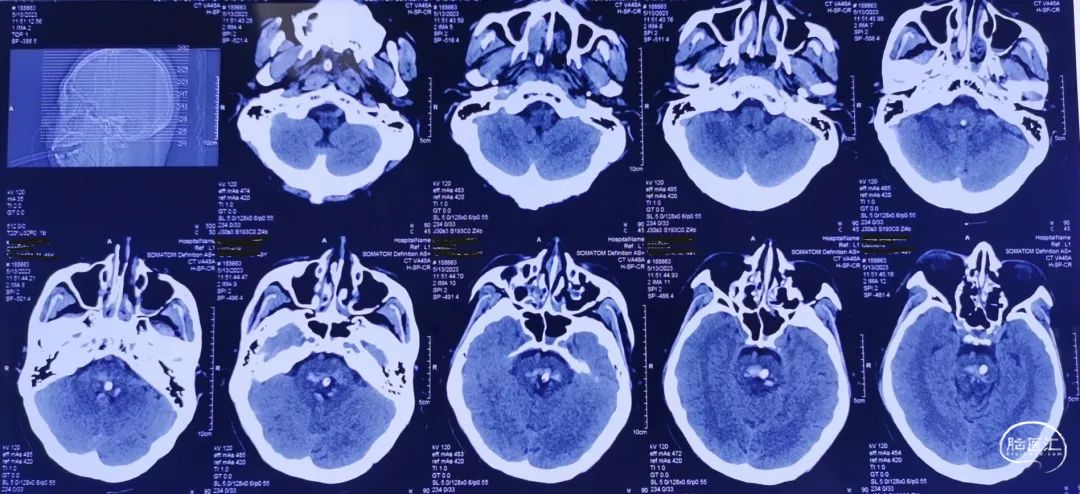

对波及大脑脚、中脑、桥脑上部的上下狭长型血肿,采用经额入路,避开侧脑室,经额叶-内囊前内侧-大脑脚入路,最好沿血肿长轴,靶点选择位置较低、血肿较大的层面;

对血肿层面较少、面积较大,主要位于桥脑中下部的血肿,选择幕下经小脑半球-小脑中脚-桥脑入路;

脑干出血往往合并中脑导水管的梗阻,经额入路可术中同步并行放置脑室引流管,经小脑入路可术中经枕叶放置脑室引流管;尤其对于脑室未扩张的病例,利用立体定向框架可准确植入脑室引流管。

CT扫描后测算脑干血肿穿刺靶点及路径

脑干血肿引流管经大脑脚入中脑

引流管穿经中脑血肿

引流管准确到达靶点

术后尿激酶应用,术后3天复查CT,血肿引流满意